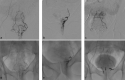

Emborrhoid: Rectal Artery Embolization for Hemorrhoid Disease

- Vidal V, Sapoval M, Sielezneff Y. Emborrhoid: a new concept for the treatment of hemorrhoids with arterial embolization: the first 14 cases. Cardiovasc Intervent Radiol. 2015;38(01):72–78. - PubMed

- Tradi F, Louis G, Giorgi R. Embolization of the superior rectal arteries for hemorrhoidal disease: prospective results in 25 patients. J Vasc Interv Radiol. 2018;29(06):884–8920. - PubMed